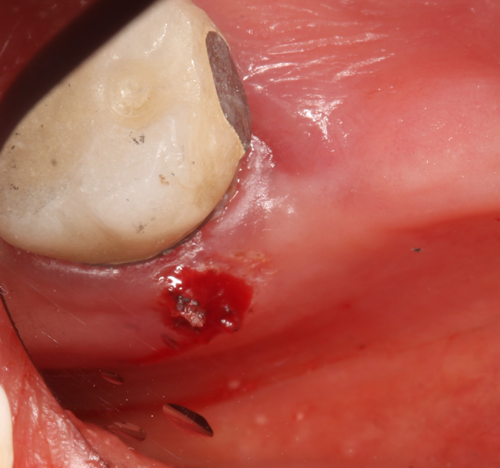

Compare this to use of the Gemini laser. We can set the power setting of the laser using the preset power settings for “Troughing” (Fig. 2) at 1.1 watts. The pre-initiated tip (pigment on the laser fiber converts some of the laser energy to photothermal energy) is placed into the sulcus to ablate the soft tissue, which creates a clear separation of the soft tissue from the tooth margin and achieves instant hemostasis (Fig. 3). We then have no need to wait and can immediately take the impression (Fig. 4). I consider this alone as priceless in my day-to-day practice.

Fig. 1 Fig. 2 Fig. 3